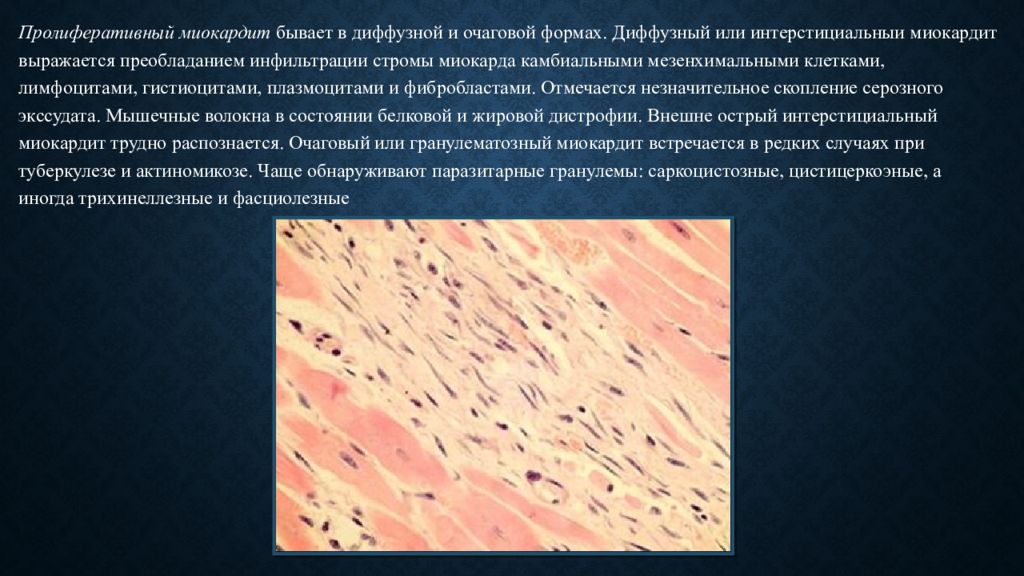

Межуточный миокардит: гистологические исследования